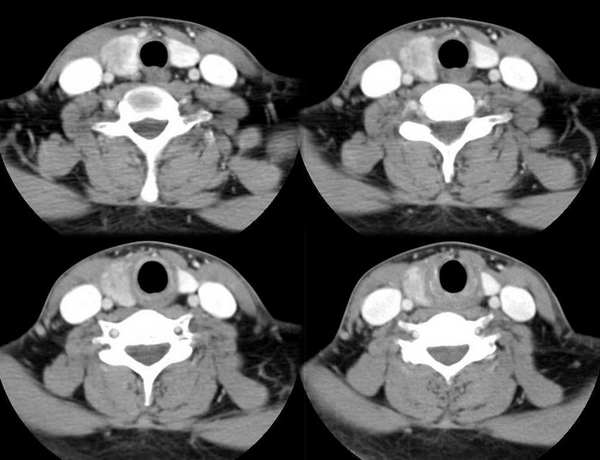

男,25岁,体温39.3度,发现右侧颈部包块.

左侧甲状腺肿大,增强时较对侧密度低。考滤炎症可能性为大。这种病灶要用影象检查时还算彩超较ct为好

临床怀疑甲状腺炎

右侧甲状腺炎

此病例特点:1、年轻男性,基本上是高热;2、右侧甲状腺肿大呈边界不清之低密度,但甲状腺境界清晰;3、基本没有增强但低密度的周边略呈边缘增强反应;4、最好补充病史:痛否?时间?(如痛、急性起病。)

据此,以甲状腺急性炎症可能性大。